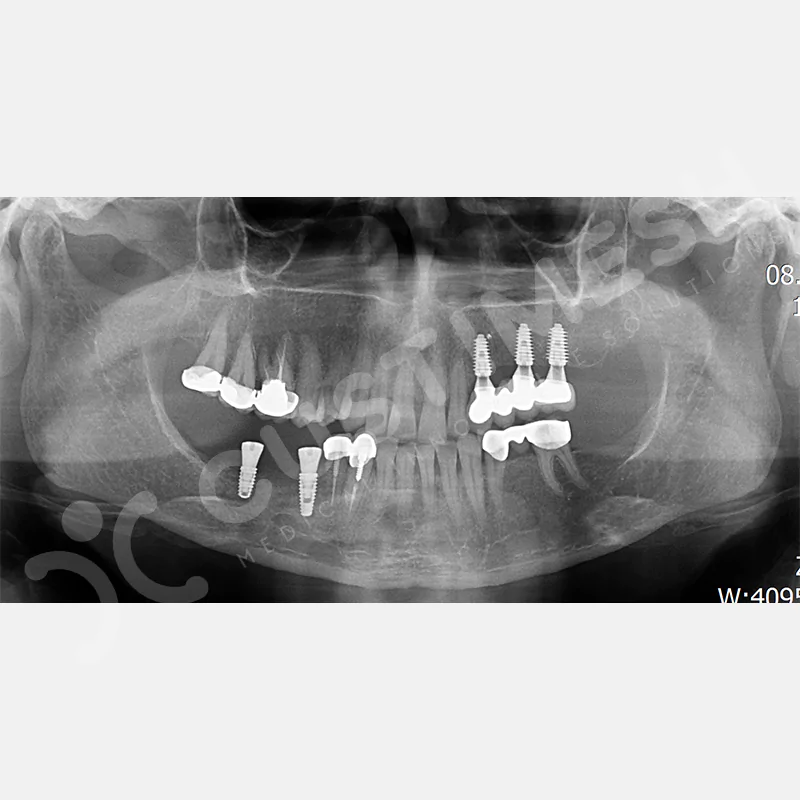

VAKA 3